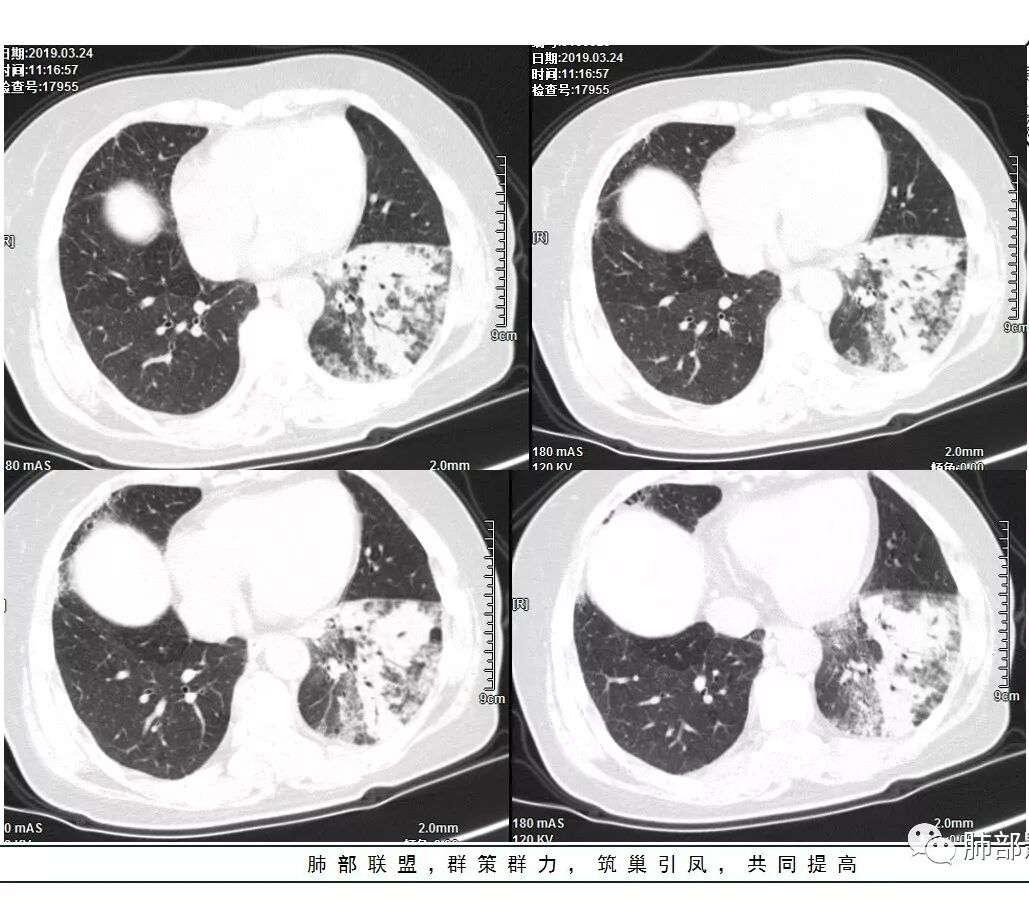

1、主病灶  左下叶斑片状、大片状致密影

2、两肺马赛克灌注

3、两侧肺门区钙化淋巴结

总共就这三大块

这三幅图是连续的,我们看到支气管中间这一幅狭窄了

大——小——大,狭窄后扩张

从这幅图看好像与周围病灶分界不清,支气管腔狭窄后扩张,支持炎性